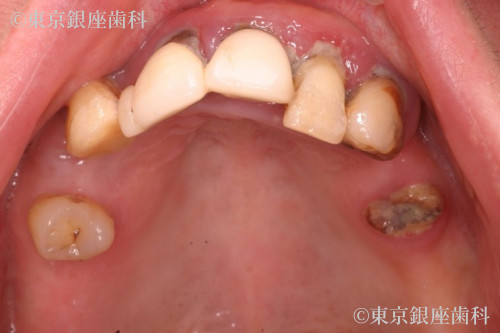

歯周病とむし歯によって咬合崩壊 上下ワンデイインプラントにて再構築した症例

Before

子供の時から歯が弱く通院を繰り返していたが、最近は人に見られるのも嫌で痛みのある時しか歯科に行かなくなった。奥歯が抜けてしまい食事ができない。口臭も気になるので人と対峙して話すことも控えるようになり仕事の面でも支障をきたす。歯肉が腫れたり、歯磨きしても痛いときがある。

歯周病の進行で歯に動揺があり長期の保存が難しく、臼歯の欠損で咬み合わせが下がって前歯部への負担が大きくなっているため全顎的な治療が必要と判断。最小限のインプラント埋入によって咬合を回復させるため上下ワンデイインプラント処置を計画。